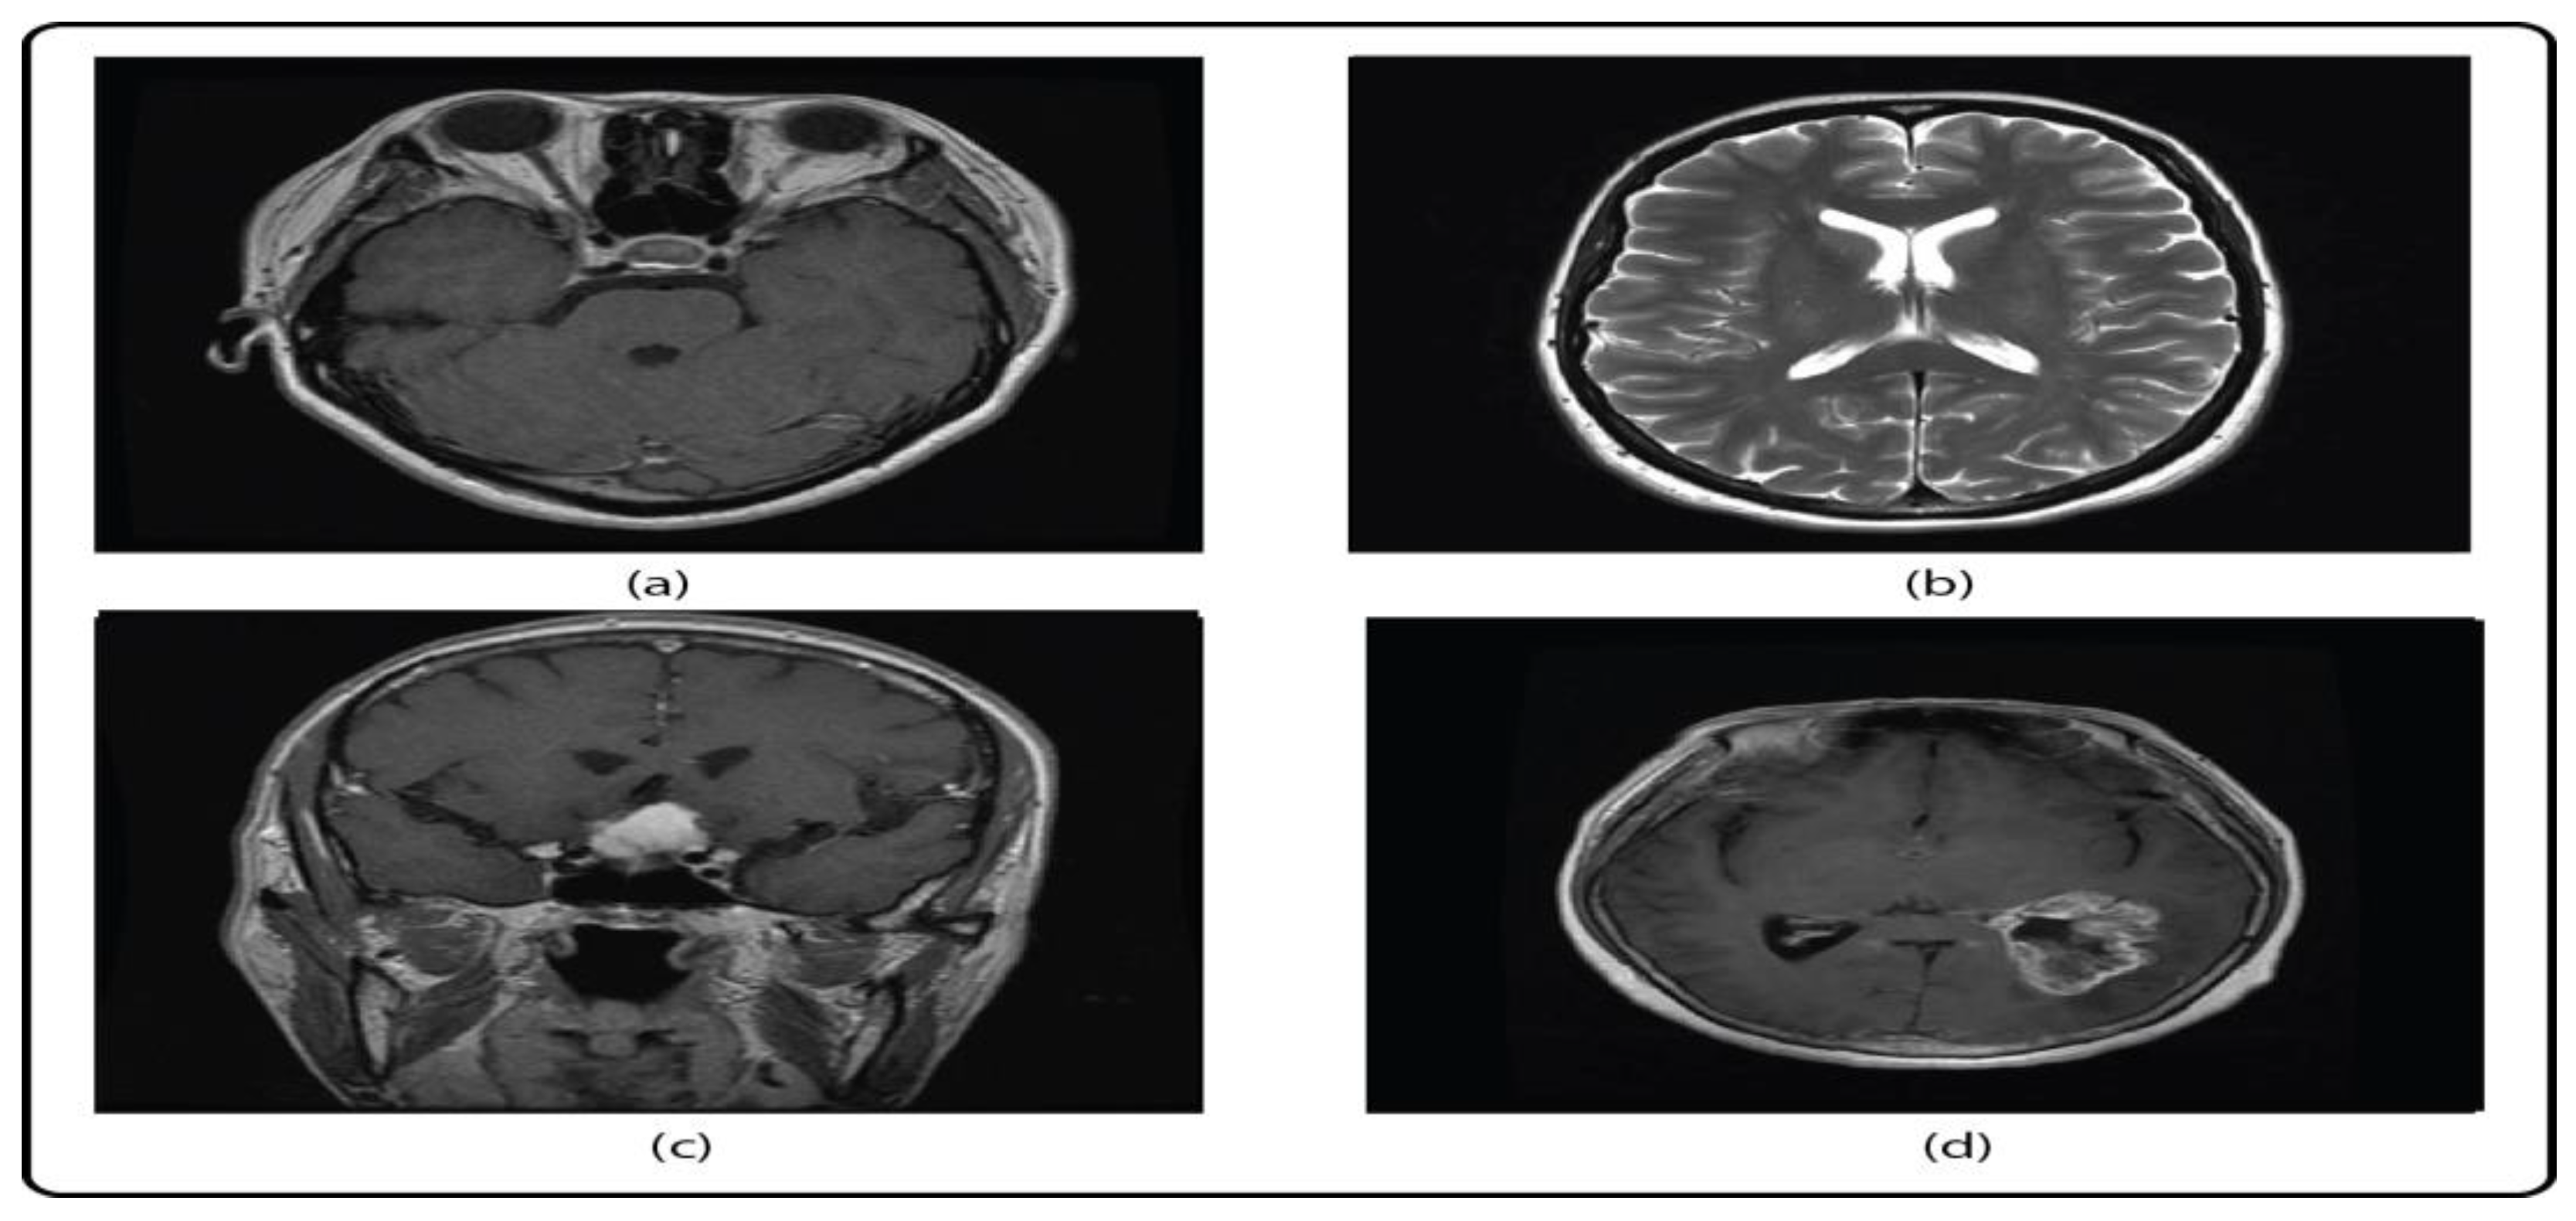

4.1. Brain Tumor Prediction Results Using Secure CNN Feature Fusion